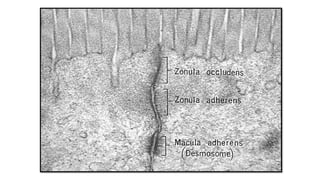

Desmosomes

(macula adherans)• DEF:

localized spot-like structures specialized for cell-to

cell adhesion. they are type of junctional complexes.

• SITE :

Randomly arranged on the lateral sides of plasma membranes.

• FUNCTION:

-Form adhesive bonds

-Gives mechanical strength to tissues

frequently subjected to mechanical forces.

• STRUCTURE:

• Thickening of 2 adjacent cell membranes.

• 2 attachment plaques.

• Tonofilaments.

• Intervening extracellular structure.